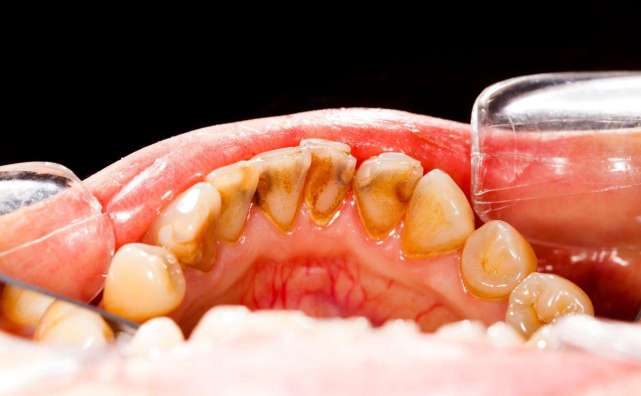

牙髓炎

引发牙髓炎的原因有龋齿、牙外伤、楔状缺损等,牙痛往往为自发性,夜间疼痛加重。

因为细菌从龋洞进入牙髓腔,引起牙神经充血、炎症。如果牙髓炎不及早治疗,甚至会造成死髓牙或引起牙根尖周炎等。

常见的龋齿、牙周炎、牙龈炎。这类疾病是什么原因引起的呢?

无论是龋齿、牙周炎还是牙龈炎,这类疾病都是由细菌所引起的慢性感染性疾病。